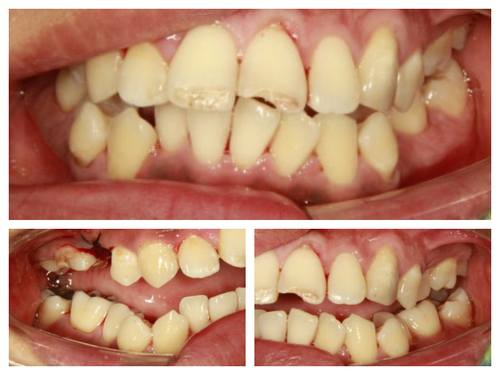

구역질이 심해서 작년에 치료를 받다가 그만두고 치아가 아파서 내원했다는 30대 남자 환자

그럼 스켈링하신지 오래 되셨고 이~하셔서 보니 앞니에도 치석이 많으니 오늘은 스켈링과 검진을 목표로 합시다.

역시 스켈링도 못 받으셨던것 같다.. 약이 들어가고 주무시기 시작해서야 겨우 구강 상태를 살필 수 있었다..

발치가 필요한 치아, 심한 충치가 있는 치아, 치료가 마무리 되지 못한 치아..

첫 날 진료가 끝나고 환자와 다시 마주하고는 양치질 하시기도 힘드시겠네요.. 했더니 정말 그렇다며 오랜만에 스켈링 받아서 입이 개운한 것 같다신다.